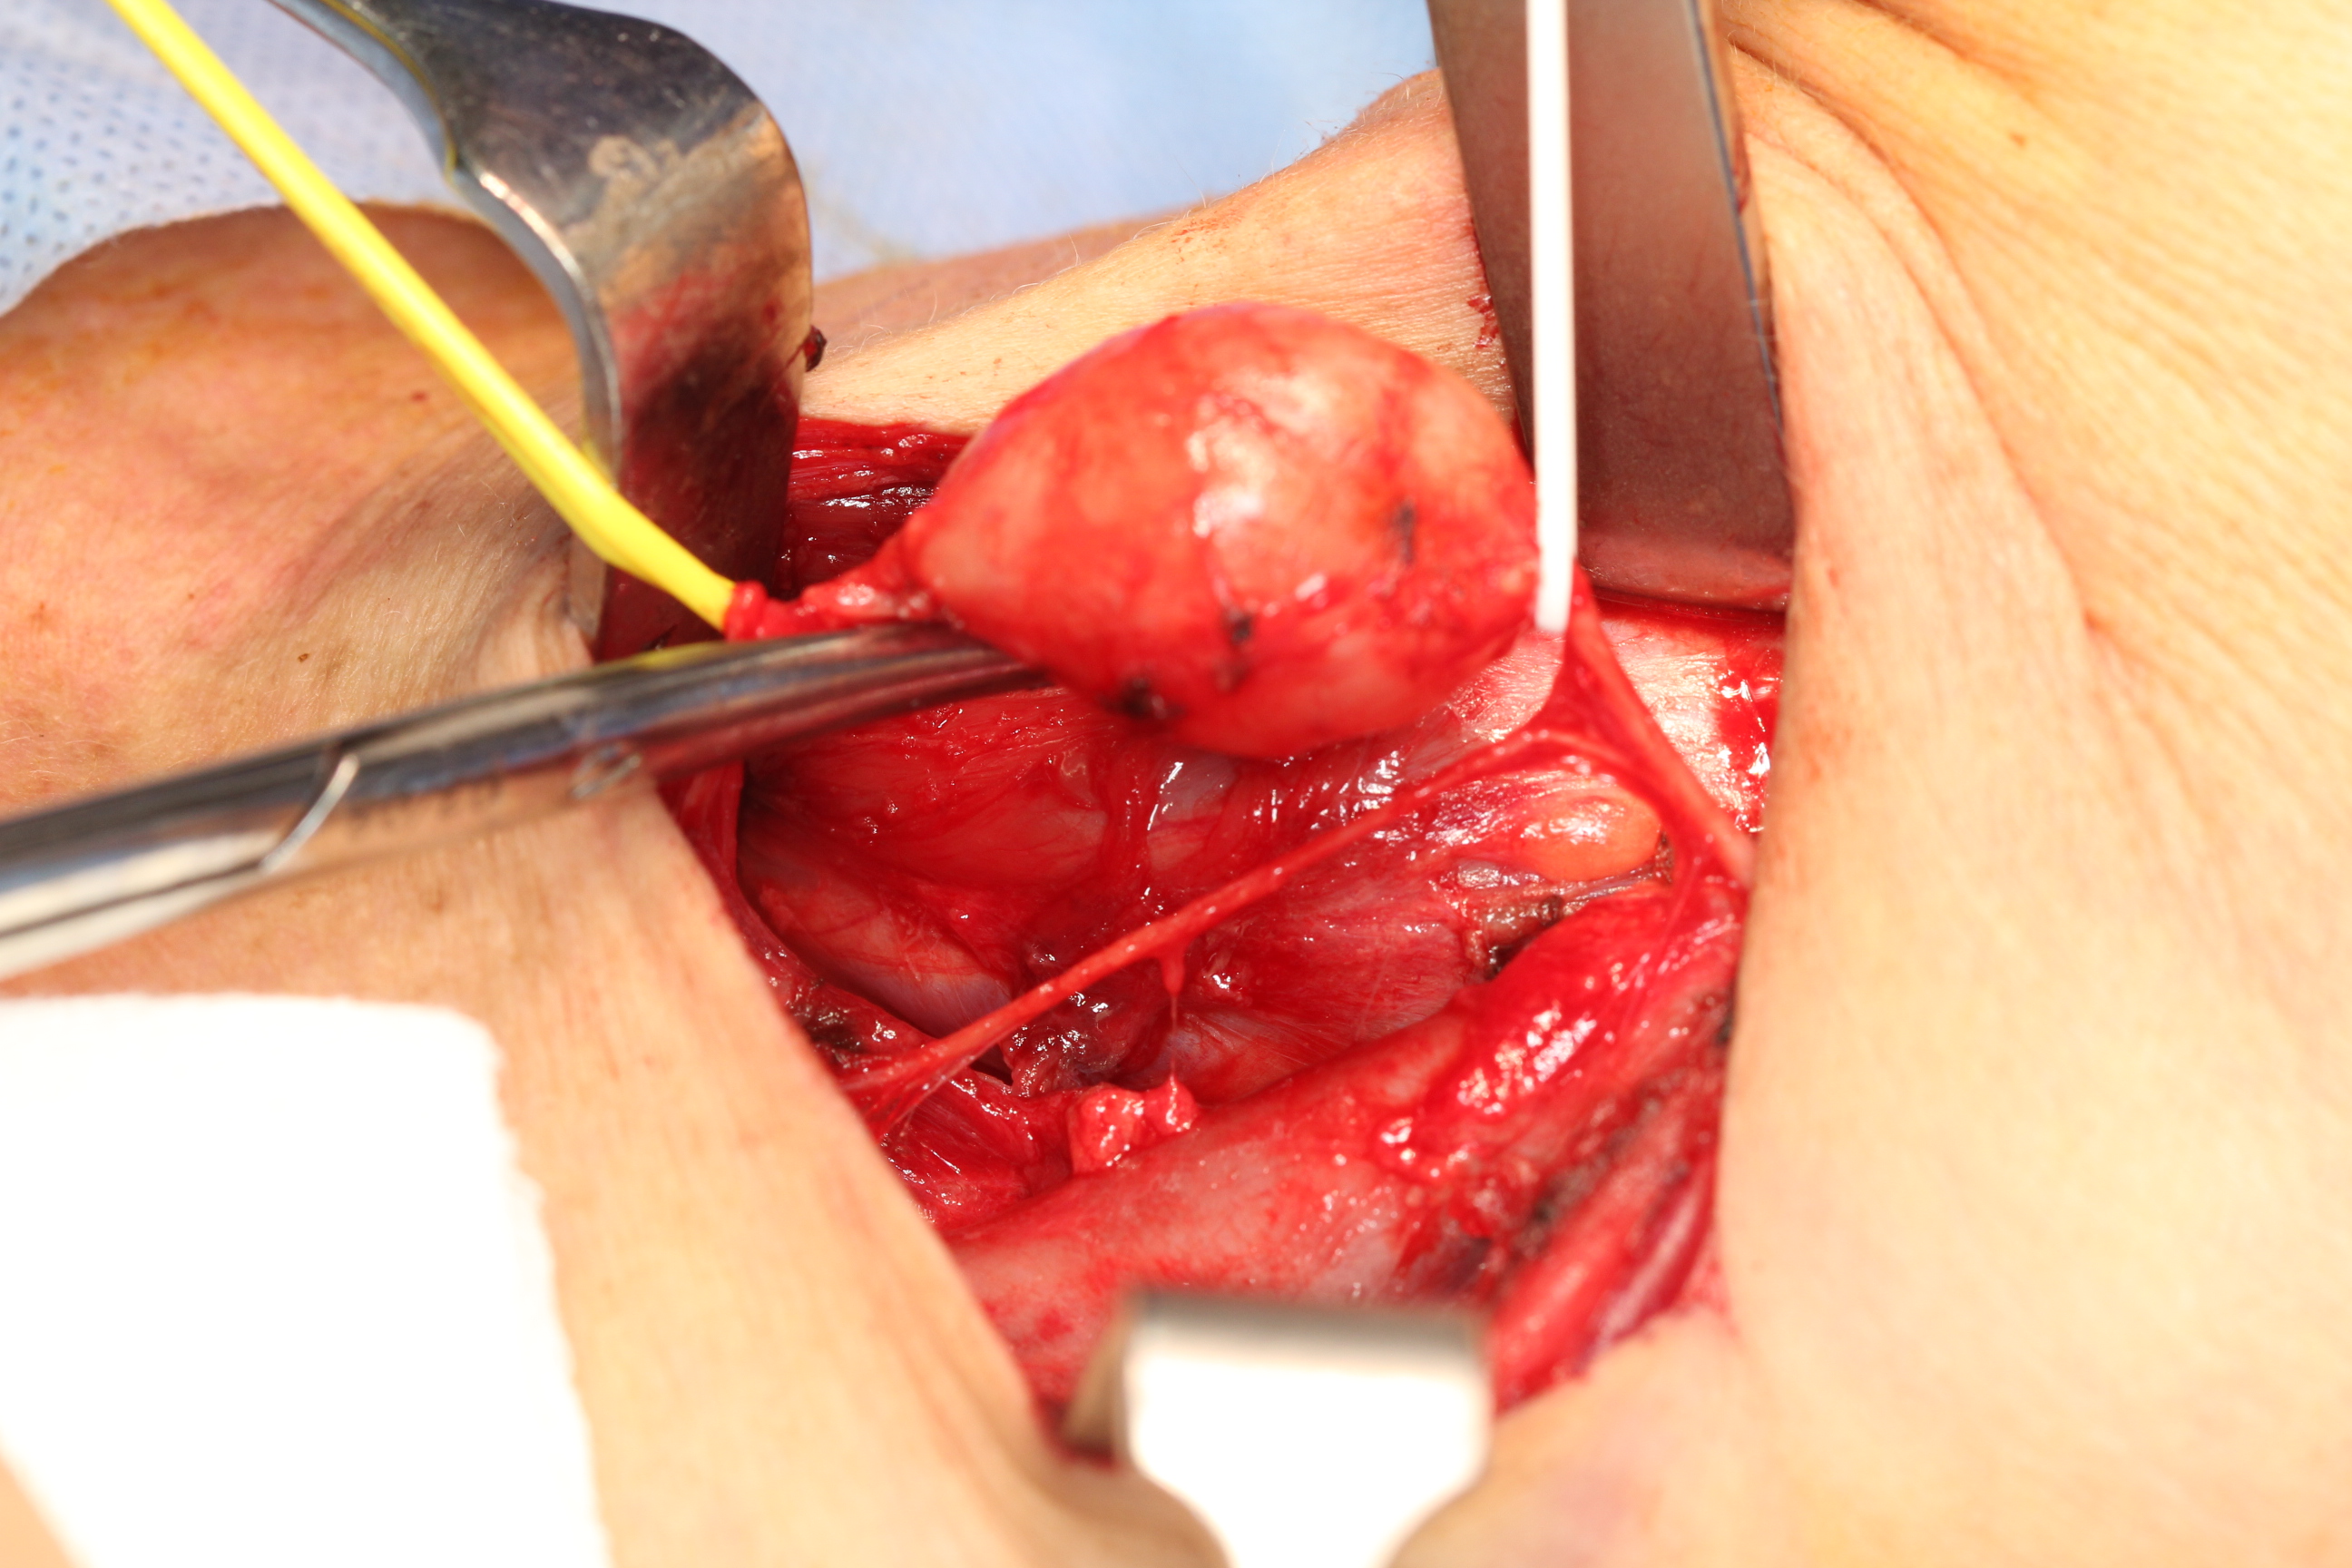

The majority of these neurogenic tumours (neurofibroma, Schwannoma) are slow-growing benign tumours. Approximately 25 to 40 % of these are found in the head and neck region. If possible / on balance, these tumours should be surgically removed: there is a small but significant risk of benign Schwannomas for malignant transformation (see Figure 3 and Figure 4).

Figure 3: Sympathetic chain schwannoma, these tumours can be very difficult to safely access and remove but this is possible without causing great damage.